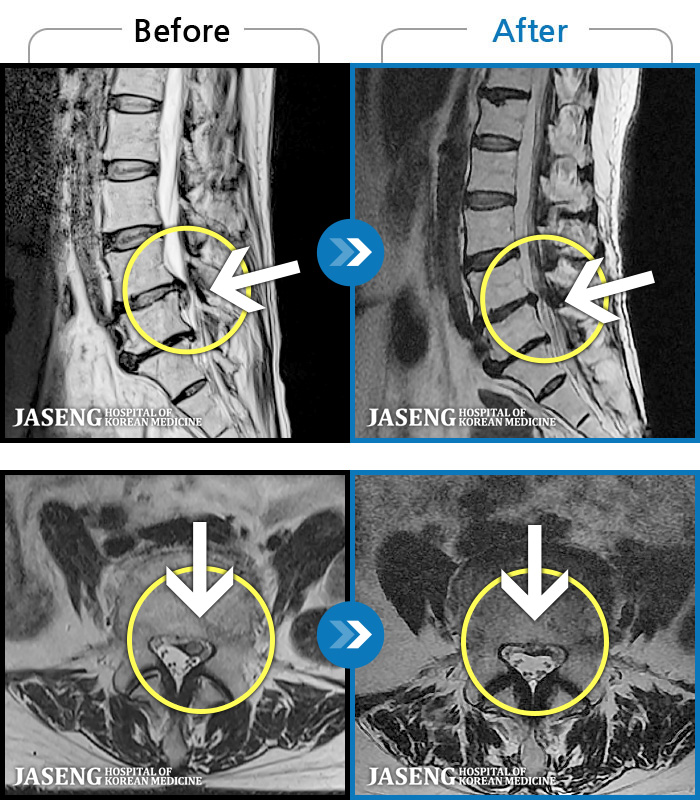

MRI ũ ʸ Ȯϼ.